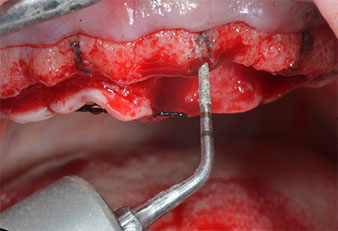

Uno strumento piezoelettrico (Piezomed I1) a forma di fiamma, rivestito in diamante, è stato usato per contrassegnare le posizioni dell'impianto e per eseguire una preparazione pilota (Fig. 3). Si è prestato attenzione a utilizzare un movimento verticale ascendente e discendente, con potenza ridotta, irrigazione completa e bassa pressione (inferiore a 300 g). Successivamente è stato applicato uno strumento pilota (Piezomed I2A/I2P) per l'ingrandimento iniziale delle sedi dell'impianto del diametro di 2 mm (Fig. 4), seguito da un inserto da 3 mm (Fig. 5).

Strumenti Piezomed I2A/I2P

Fig. 4: il prossimo passo è l'allargamento pilota con gli strumenti Piezomed I2A/I2P, che vengono applicati con un movimento orizzontale rotatorio.